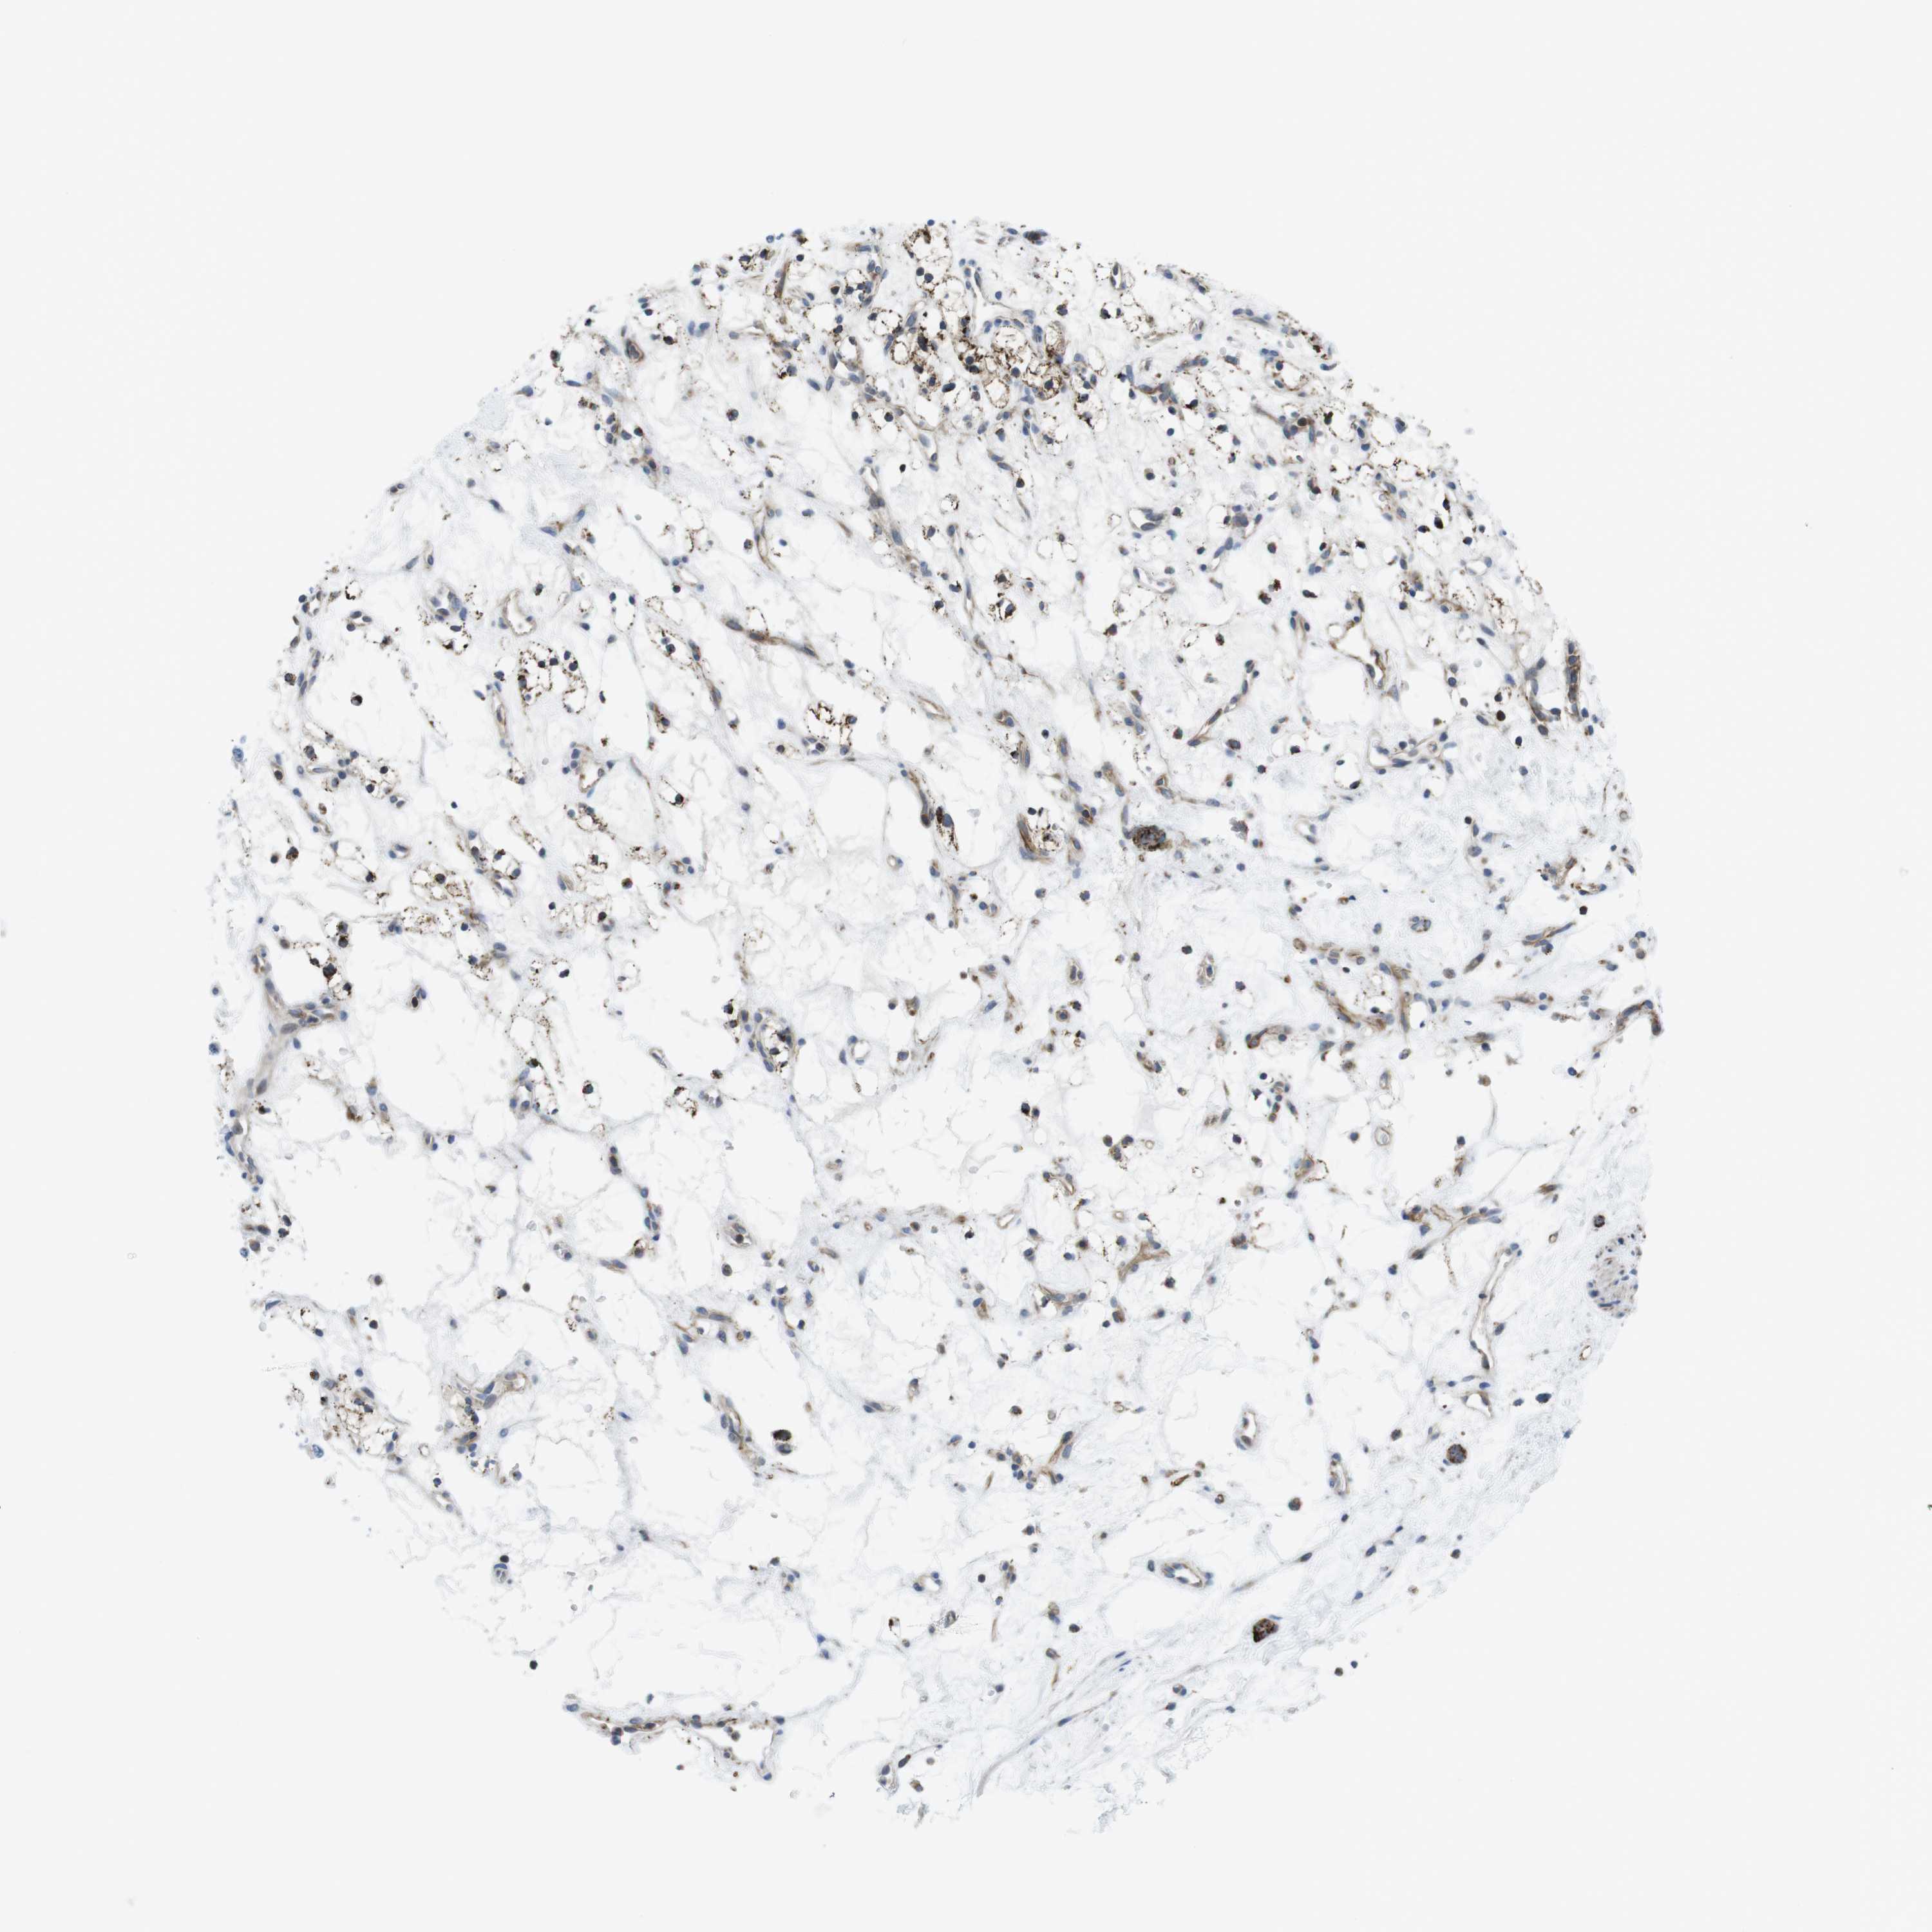

Average pTPM 115.6

Number of samples 100